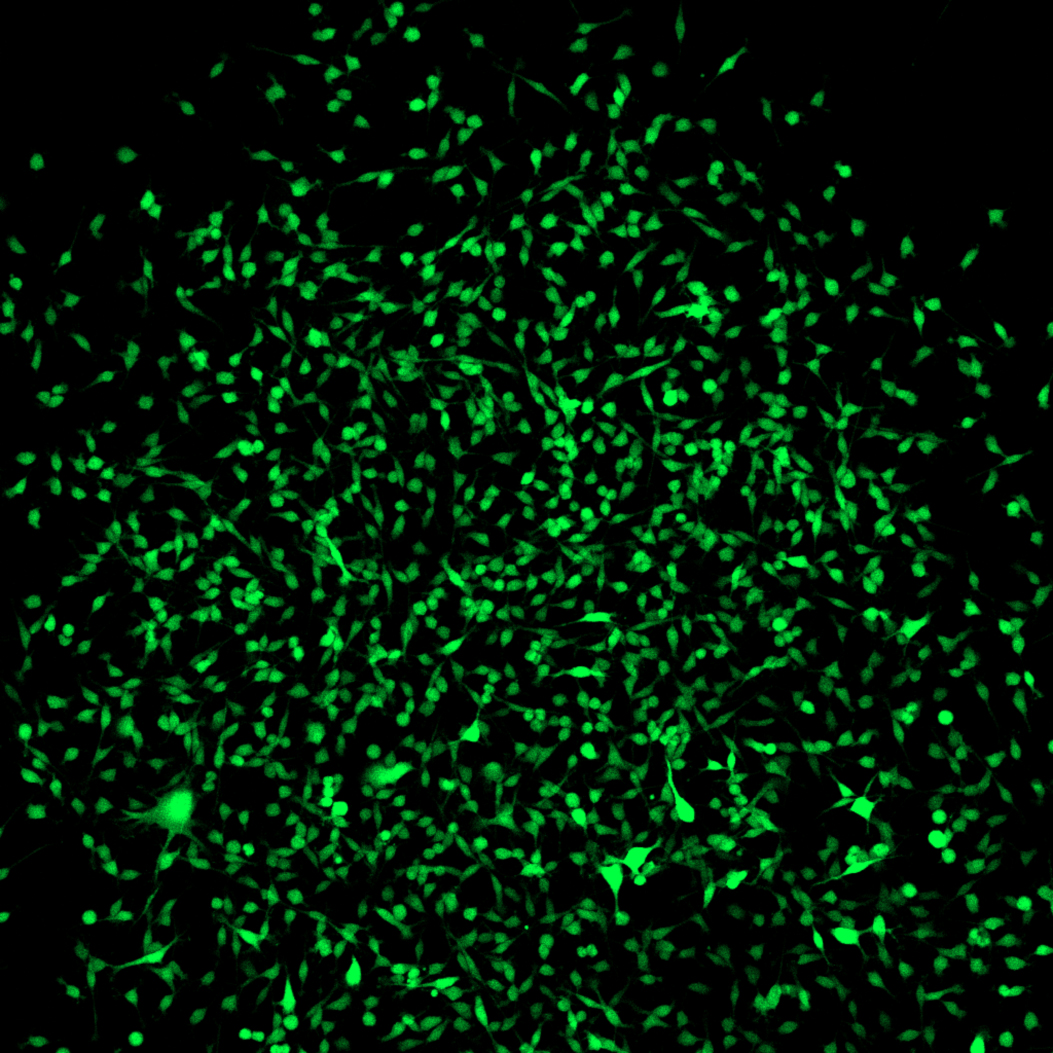

They then generated transgenic mice, where expression of the CD73 gene results in green fluorescent labeling of the respective cell. “As CD73 is mainly active in the multipotent stromal cells, these are marked by a green glow”, explains Breitbach's co-author Dr. Kenichi Kimura.

The dye-labeling made it possible to isolate these cells from the bone marrow. The scientists were then able to show that bone, fat and cartilage cells differentiate from a single multipotent stromal cell in the culture dish. “Our method makes it possible to examine the cells in their original state”, says Breitbach. “In future studies, it will for example be possible to clarify directly in the living animal whether and how the stem cells migrate to the different organs in the case of injury or illness, and what they do there.”